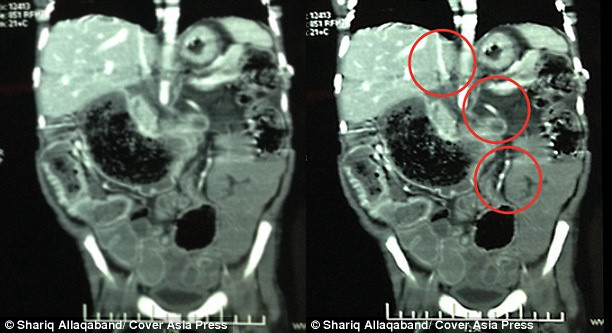

Bà quyết định đưa cậu bé đi chụp X-quang ngay lập tức và kinh ngạc phát hiện vật thể lạ là một búi tóc dài tới 1,22 mét trong dạ dày Sivam.

Tiến sĩ Sharma cho biết: "Có rất ít khí ở vùng bụng. Búi tóc đã lan khắp dạ dày và len lỏi cả vào ruột cậu bé. Chúng tôi đã phải tiến hành phẫu thuật và lấy ra được một búi tóc có hình dạng gần như trùng khớp với hình dạng bên trong dạ dày".

| Phim X-quang cho thấy hình ảnh búi tóc chiếm hầu hết dạ dày và lan cả xuống ruột. (Ảnh: Cover Asia Press) |